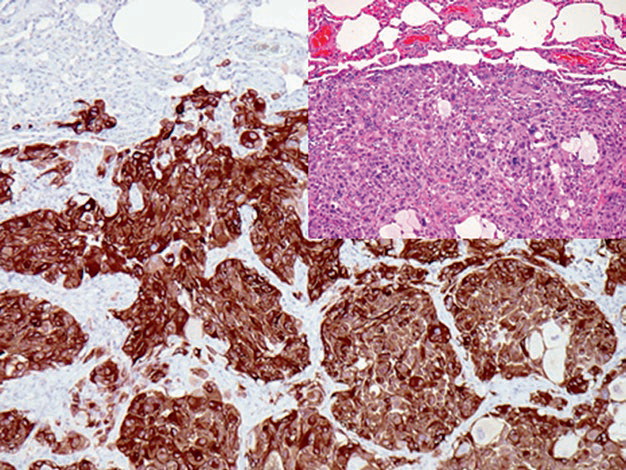

图片

Figure 1. Metastatic malignant melanoma, HMB45 positive.

It should be noted that approximately 10% of malignant melanomas do not express HMB45, especially in amelanotic malignant melanoma, desmoplastic malignant melanoma, and spindle cell malignant melanoma, where this proportion is higher. The combined use of multiple malignant melanoma-related antibodies can significantly improve detection sensitivity, such as the combination of HMB45,Melan A, and tyrosinase. Additionally, some tumors with morphological similarities to malignant melanoma may also express HMB45, such as adrenal pheochromocytoma and clear cell tumors of the lung, but these tumors generally do not express tyrosinase or SOX-10.